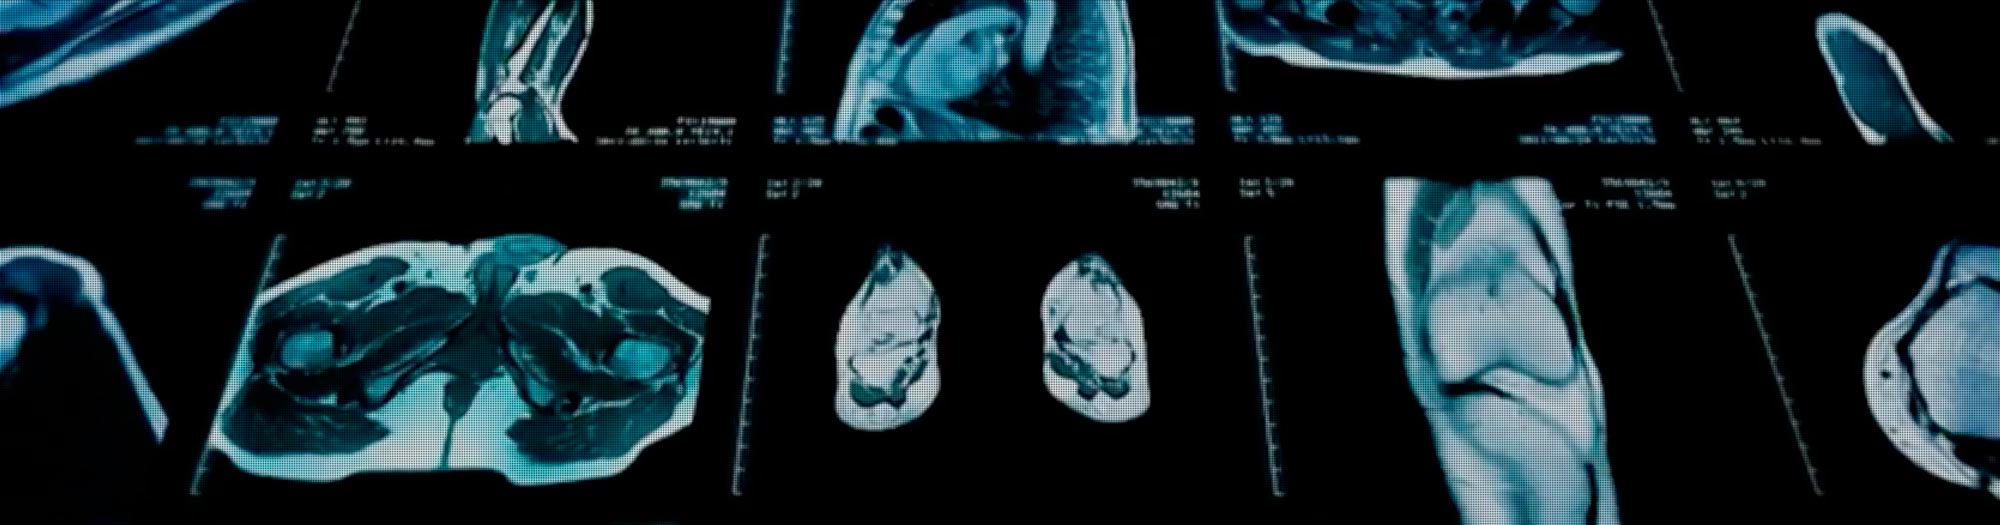

Resonancia Magnética

Ecografía Rayos X con Precios del 2025

Gnostika es un centro de imágenes diagnósticas fundado por médicos especialistas con experiencia y reconocimiento.